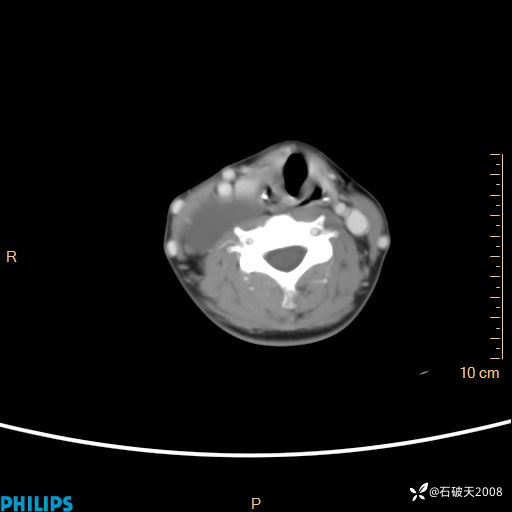

影像诊断要密切结合临床,真的很有必要(病理已公布)

女 21岁 主 诉:发现右侧颈部肿物18年余。

现病史:18年余前患者无明显诱因发现颈部偏右侧有一肿物,具体大小不明确,咳嗽、憋气时肿物增大,局部无疼痛,无吞咽不适,无胸闷及呼吸困难,至当地医院检查考虑良性病变(具体不详)并未做特殊处理,现患者自觉肿物随年龄增长而进一步变大,今日至我院行颈部CT平扫+增强提示:1.右侧颈根部、锁骨上窝及纵隔内异常密度影,考虑良性病变,淋巴管瘤?囊肿?请结合临床。2.双侧颈部小淋巴结。建议结合临床及其他相关检查。现为行进一步治疗,门诊以“颈部局部肿物”为诊断收住我科,发病来患者神志清,精神可,饮食睡眠可,大小便正常,体重无下降。

平扫